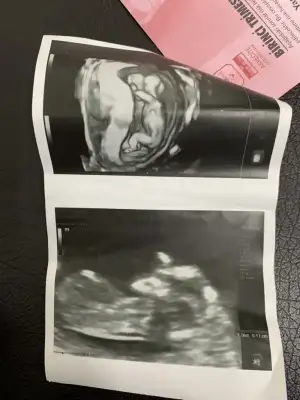

Bu da arkadaşımın bebişinin 12. haftasından görüntüsü. Yine tahmin rica edeceğiz sizden. Sevgiler

Eklentiler

• M 12 hafta.webp

M 12 hafta.webp

10,9 KB · Görüntüleme: 54